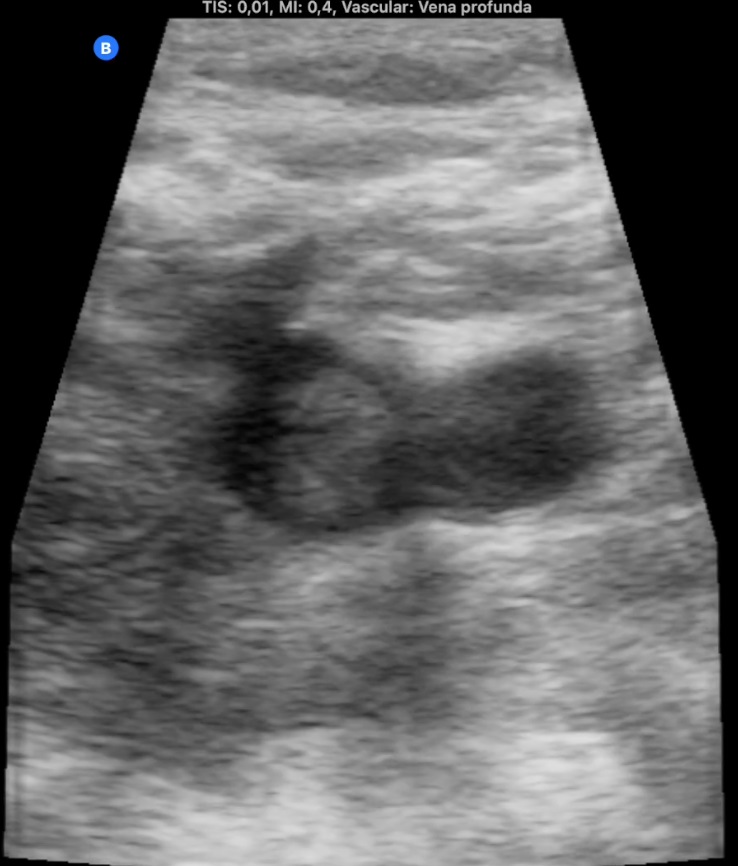

La ecografía pulmonar muestra microconsolidación y líneas B en campo posteroinferior derecho (imagen 1). Ante el antecedente de inmovilización y TEP previo, preguntamos por edemas y refiere inflamación en miembro inferior izquierdo, constatándose cierto aumento de perímetro. La ecografía de MII muestra trombo hiperecogénico femoropoplíteo con captación de Doppler periférico (imagen 2, 3 y 4).

TEP y TVP secundarios a inmovilización.